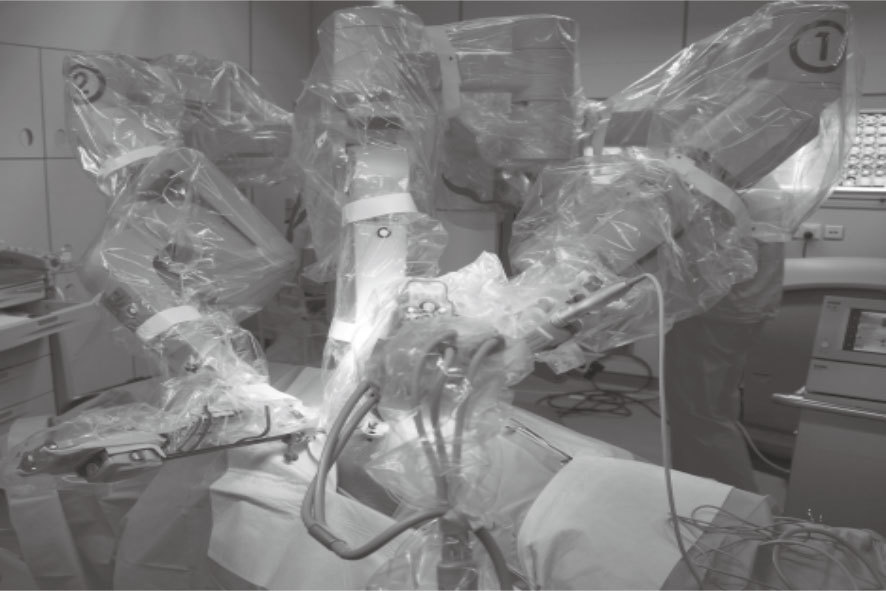

全身麻醉誘導同時,由經過專門培訓的護士啟動機器人外科輔助系統da Vinci S,完成系統自檢和預熱,套好無菌袋,備好用于手術操作的機械臂待命。機器人前縱隔腫瘤手術根據病變主體部位的位置,決定經右或左胸徑路( 靠近病變部位)。對側橈動脈穿刺建立動脈血壓監測,全身麻醉后雙腔氣管內插管。患者術側胸部抬高45°、同側上肢置于半垂固定體位(圖 1),充分暴露術側胸部。穿刺右側頸內靜脈建立大靜脈輸液通路,監測雙上肢經皮血氧飽和度,常規留置導尿管。